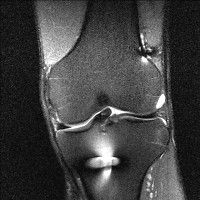

무릎 mri 간단히 봐주실 수 있으시나요 ㅠㅠ

안녕하세요 8년전 십자인대 수술하고 최근 무리한 운동에 무릎 불편감이 생겨서

mri 찍었습니다.

진단결과는 첫 찍은 병원에서 활액막염 이라는 진단을 받았습니다. 혹시 봐주실 수 있으실까요?

올라온 MRI가 단편적이라서 정확한 진단에 어려움이 있지만 십자인대에는 큰 이상이 있지는 않은것 같으며, 무릎관절내 물이 있는 것으로 보아 활액막염의 진단이 맞을 것 같습니다.

하지만 단편적인 영상이기 때문에 촬영병원에서 정확한 판독지 등을 받으시는 것이 좋겠습니다.